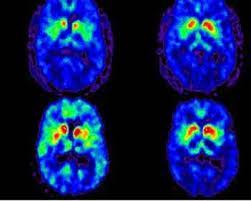

Le patient n'a pas besoin de porter d’appareil, ni de modifier son comportement. Les chercheurs ont utilisé ces appareils pour mener une étude à domicile d'un an avec 50 participants. Ils ont montré qu'en utilisant des algorithmes d'apprentissage automatique, un clinicien pouvait suivre la progression de la maladie de Parkinson et la réponse aux médicaments plus efficacement qu'il ne le ferait avec des évaluations périodiques en clinique. Rappelons que la maladie de Parkinson touche déjà 10 millions de personnes dans le monde et est le trouble neurologique qui se développe le plus vite sur la planète...